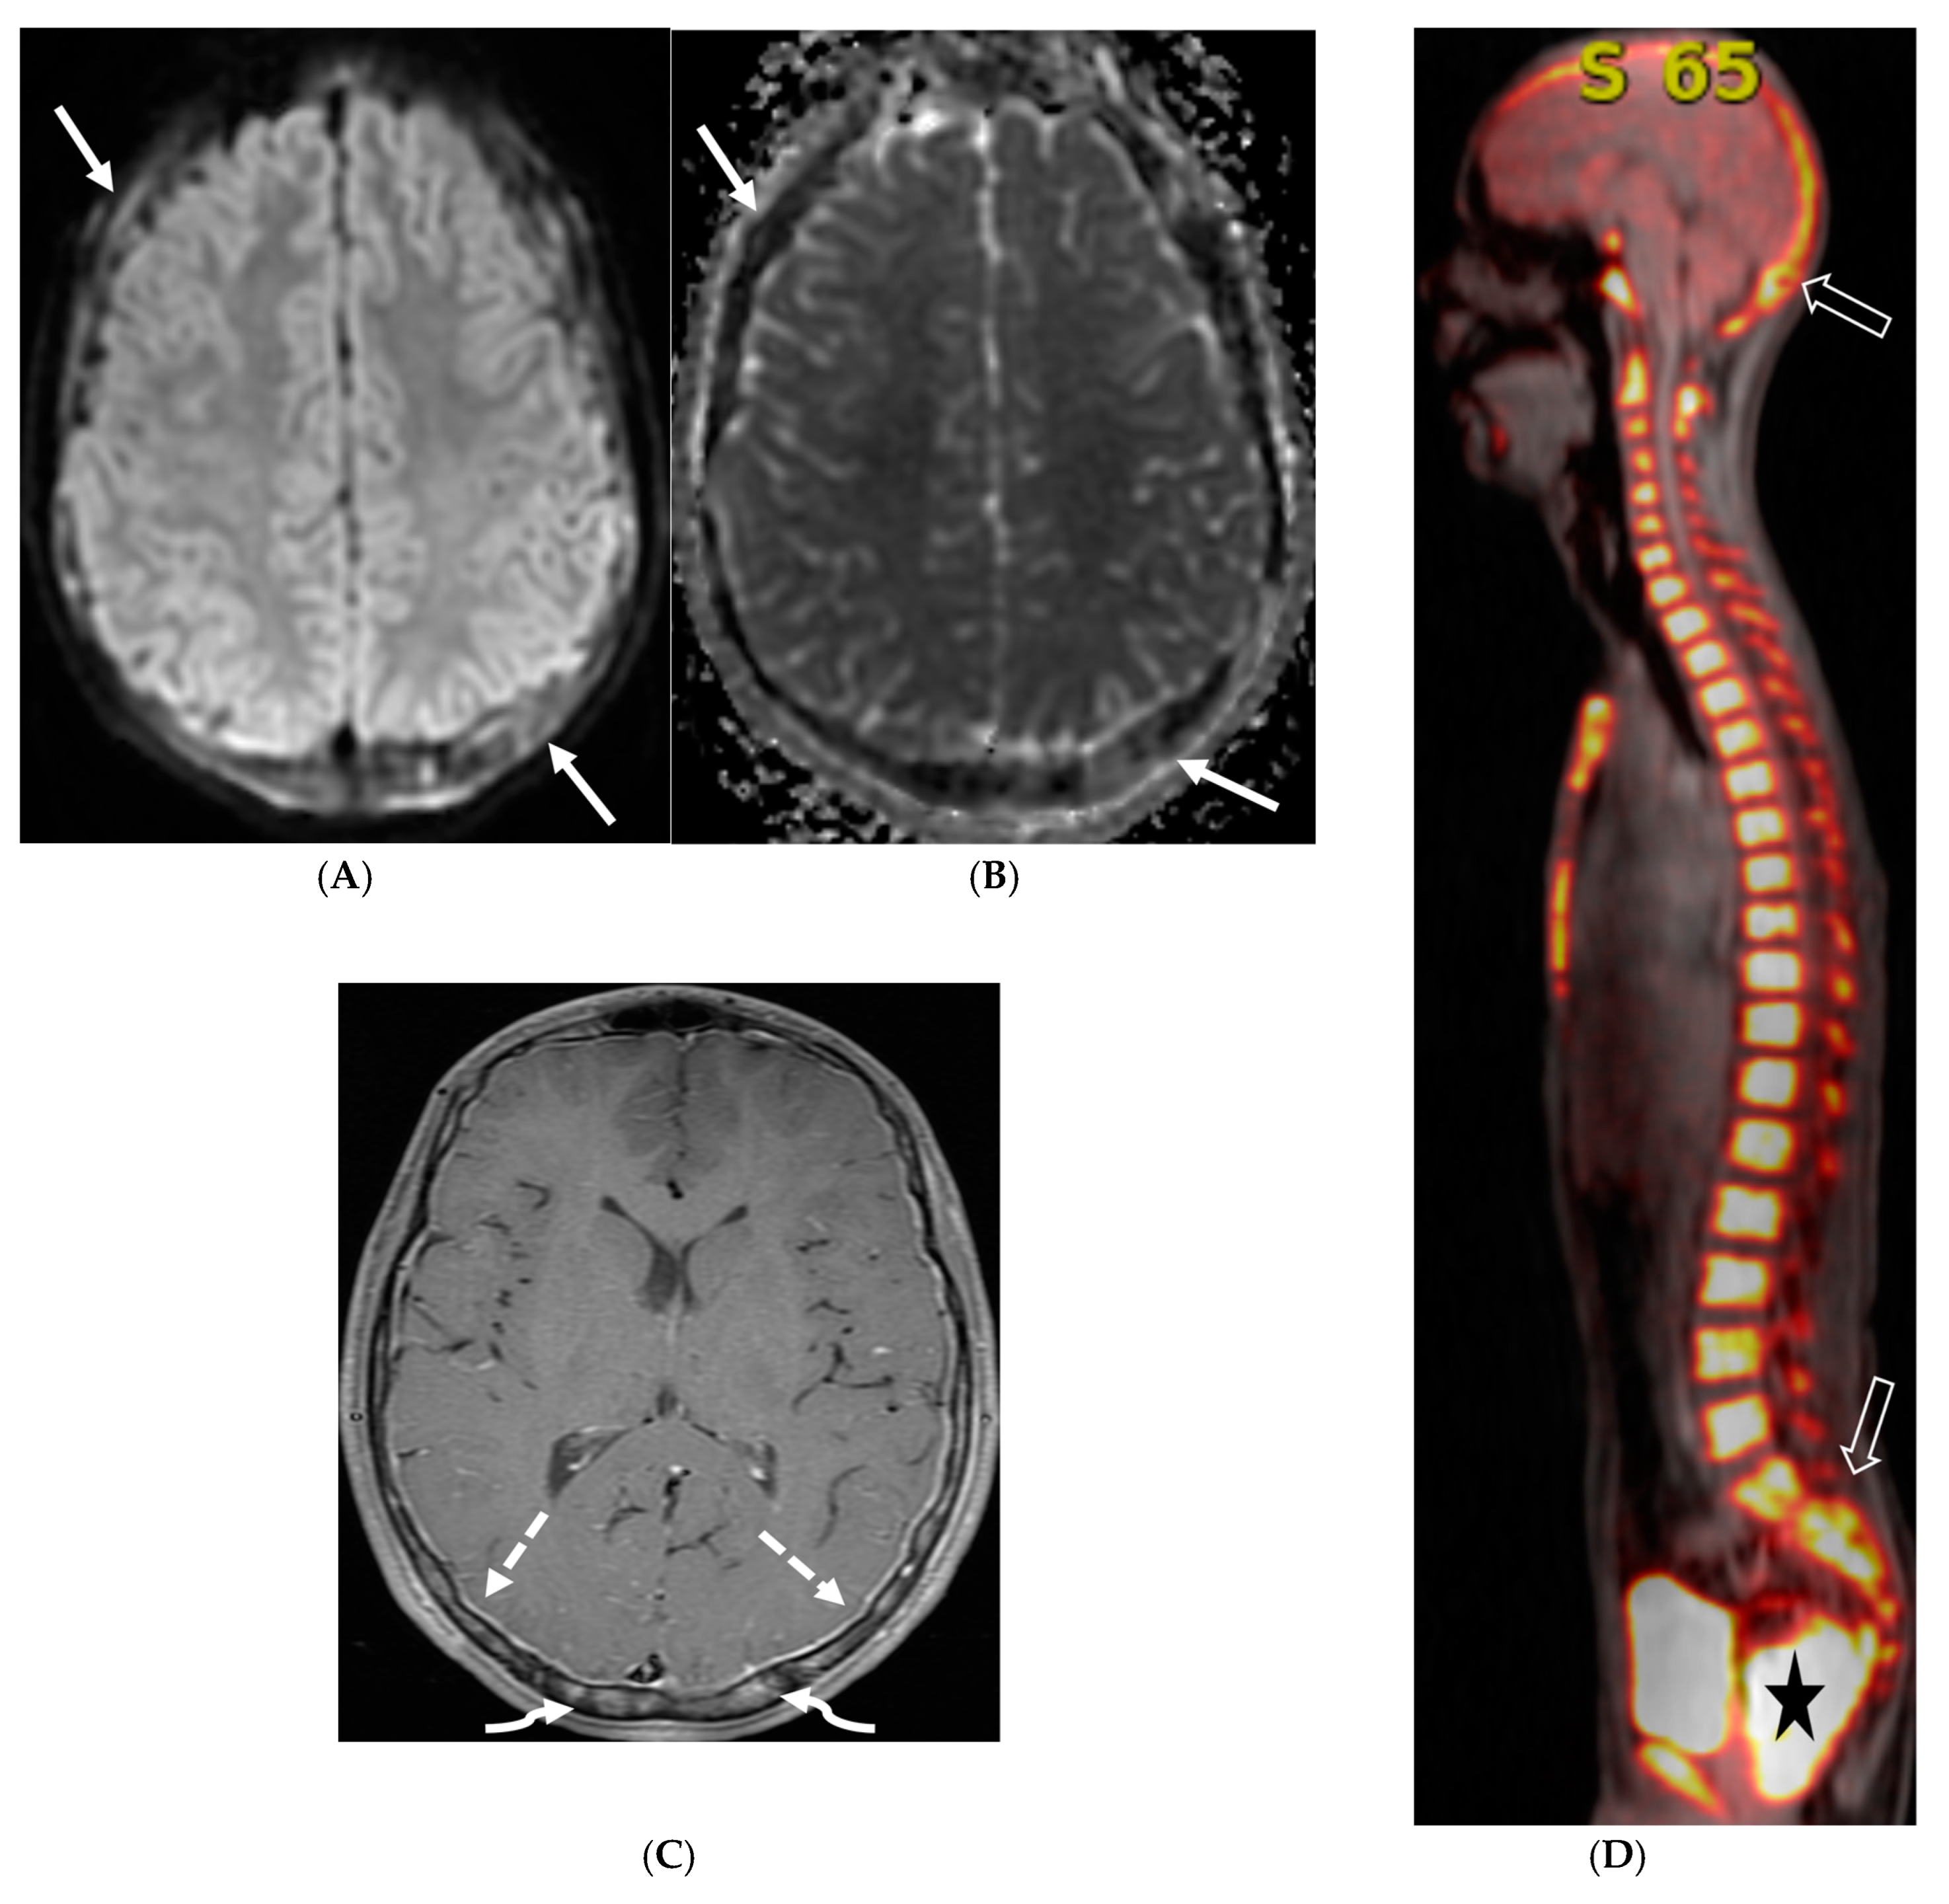

Figure 15.

Axial DWI (A), axial ADC (B), axial T1 FS post contrast (C) and Fluorodeoxyglucose Positron Emission Tomography (FDG–PET) scan (D): 13-year-old male with bilateral leg pains, headache, fever and weight loss: Blood tests and CT scan were concerning for Burkitt’s lymphoma. There is heterogeneous calvarial bone marrow signal with restricted diffusion (arrows) and patchy enhancement (curved arrows). Diffuse thickening and enhancement of pachymeninges in the supratentorial compartment is noted (dashed arrows). Findings are most consistent with lymphomatous involvement. Multifocal diffuse/heterogeneous pattern of FDG uptake within the axial and appendicular skeleton and the calvarium (open arrows). Intense FDG avid uptake is seen in the presacral mass (star).